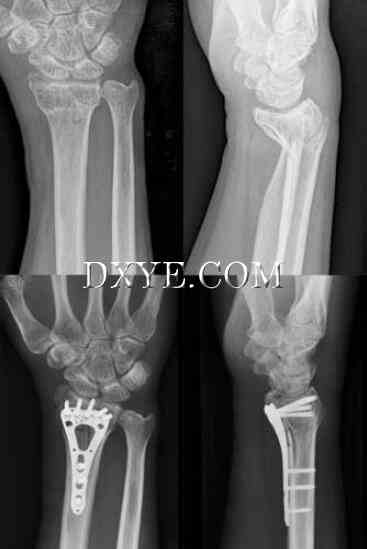

切开复位内固定。开放复位和钢板固定可以直接减少骨折,维持固定的减少,并伴随着固定时间的缩短和腕关节功能的恢复。 已经描述了掌侧桡骨的背侧和掌侧入路。 背侧入路采用与Lister结节一致的纵向切口。 第三个伸肌室打开,拇长伸肌(EPL)皮下移位。 第二和第四隔室从远端半径升高以露出骨折。 掌侧入路采用桡动脉与桡侧屈肌腱(FCR)之间的标准亨利方法,保护FCR尺侧的正中神经的掌侧皮肤分支。 拇长屈肌(FPL)尺骨缩回,前旋方向(PQ)沿桡骨径向切开,作为尺骨瓣增高以暴露骨折。

传统上采用背侧入路,因为这使得板块支撑背部移位的骨折。背侧入路可以直接观察关节面,可以同时治疗腕掌韧带损伤,是背部剪切骨折不可或缺的部分。由于骨 - 骨头更薄且经常粉碎,所以从背部移植骨也更容易。然而在20世纪90年代后期和21世纪初,背板失宠,因为早期的背板与软组织并发症相关,因为伸肌腱与桡骨远端接近。这导致肌腱刺激或破裂,并且通常需要常规移除板或其他程序。另外,使用非锁定背板后的早期运动可能会导致远端螺钉松动,特别是骨干旋转的干骺端粉碎患者。然而,与手掌钢板相比,新型的低位背侧锁定钢板在保持复位后骨折固定方面同样有效,而不会增加并发症风险(图76.15)。

目前,绝大多数手外科医生偏好大部分桡骨远端骨折的手掌入路(图76.16)。 PQ在植入物和屈肌腱之间形成屏障,使肌腱并发症发生率最小化。 锁定螺钉的固定角板能够更有效地保持下降,提供软骨下支持,即使存在骨质疏松性骨质,也能抵抗二次移位。 与背侧平皿法相比,对骨移植的需求减少。 手掌入路不可能直接观察到关节面,必须注意不要将手掌腕韧带从桡骨远端抬起。 平皿法不是没有并发症。 不正确放置的板可能会导致板的远端边界处的FPL的刺激和破裂。 螺丝尖端过度会导致伸肌腱断裂。 也有远端软骨下螺钉穿透关节的风险。

15.jpg

图 76.15.  在一个粉碎的关节内桡骨远端骨折患者(AO C3型)中使用低位背侧锁定钢板。

16.jpg

图 76.16.  使用低剖面的掌侧锁定板来解决局部关节的桡骨远端骨折(AO B3型)。